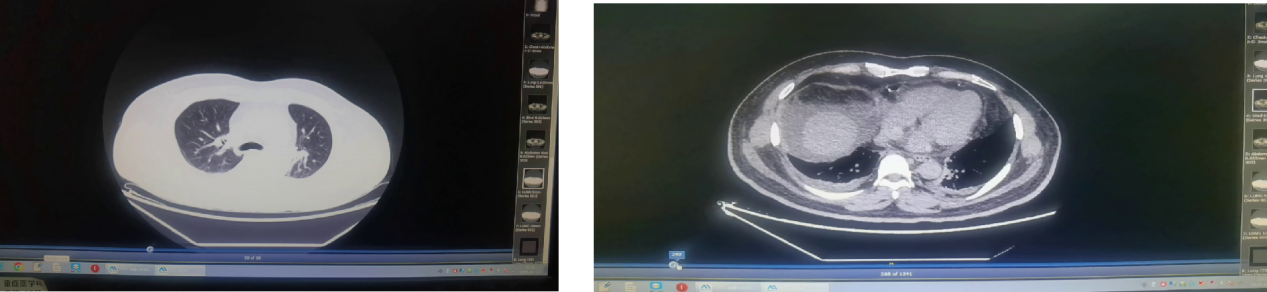

图4 影像学检查结果(5月21日)

图8 影像学检查结果(5月26日)